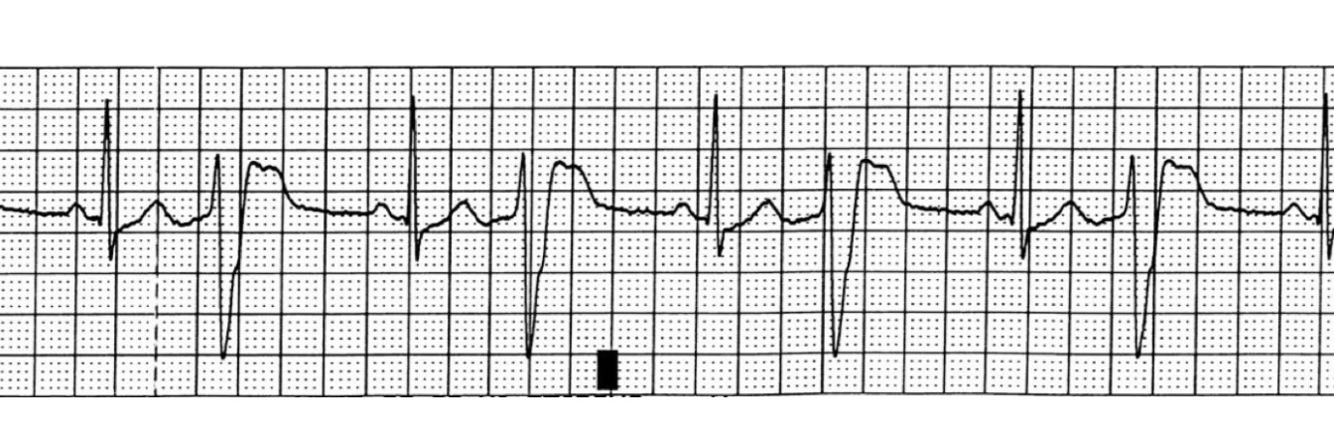

bigeminy - PVCs